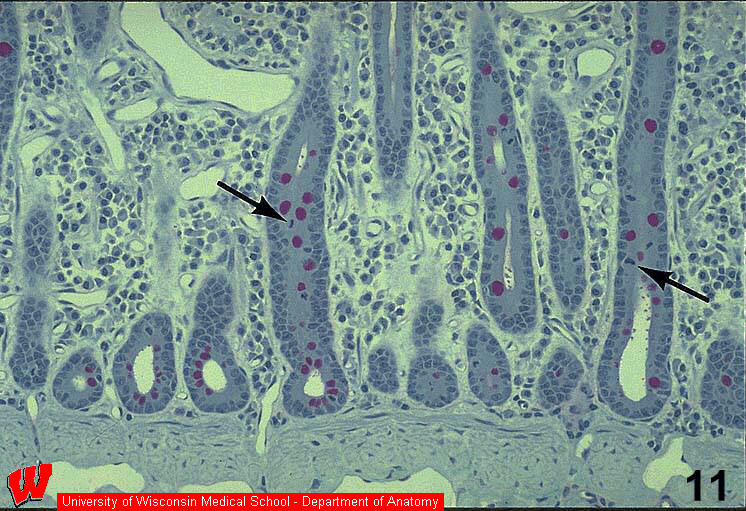

The image in HA6 is deep in the wall of the ileum and shows many crypts cut in different planes of section surrounded by a CT layer called the lamina propria. Cells in the crypt divide ( HA6, arrows ) and "push" the epithelium toward the tip of the villus in the process of cell turnover (HA6) . The mitotic cells in this part of the epithelium provide a constant supply of new cells, while other cells are being sloughed into the lumen at the tip of the villus (HA7, arrows) . This epithelium is replaced completely every 5-7 days. What are the darkly staining structures in the mitotic cells at the tips of the arrows in HA6 ?